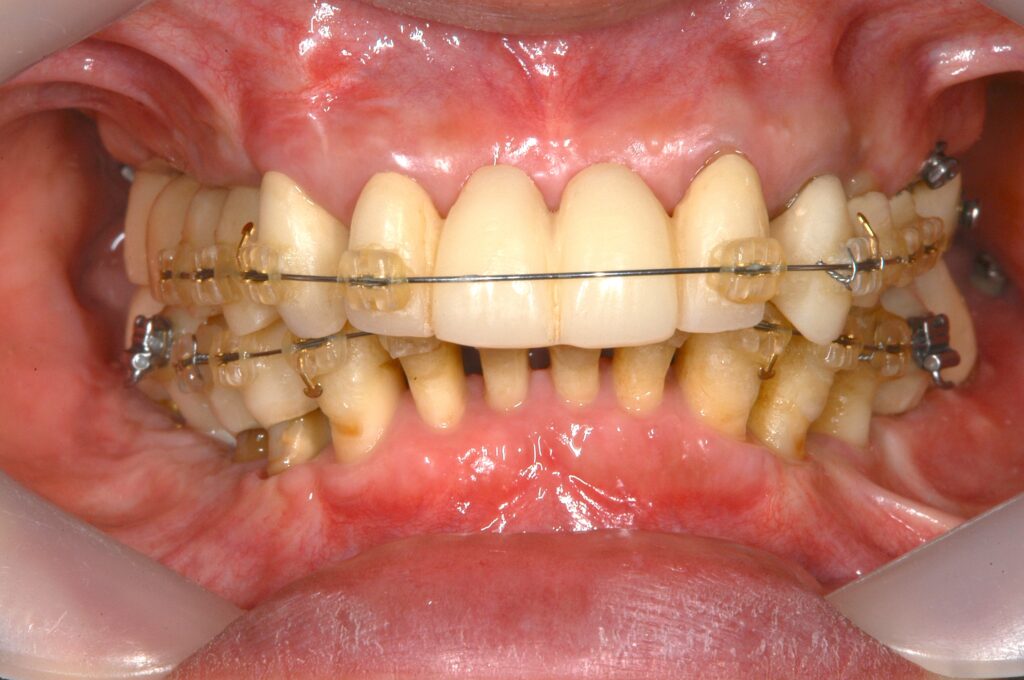

治療中①(下顎も矯正を行いました)

上下ともにPAOOというOPEを行い、薄い骨を補填しました

また骨をわざと傷つけて骨代謝を利用し、歯が骨の中を移動しやすくしました